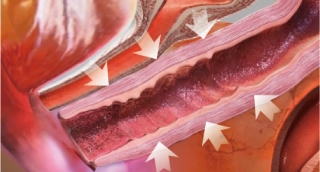

Thermal stimulation of entire vaginal wall layer

Immediately after treatment, shrinkage of the vaginal skin fibers occurs. In addition, collagen growth is promoted and the vaginal wall becomes resilient and thick. Changed Vaginal structure after treatments makes its whole conditions better.

Effect of Laser Treatment Collagen Stimulation

- Vaginal Remodeling

- Vaginal Dryness

- Sexual Dissatisfaction

- Pelvic Organ Prolapse

- Urinary Incontinence